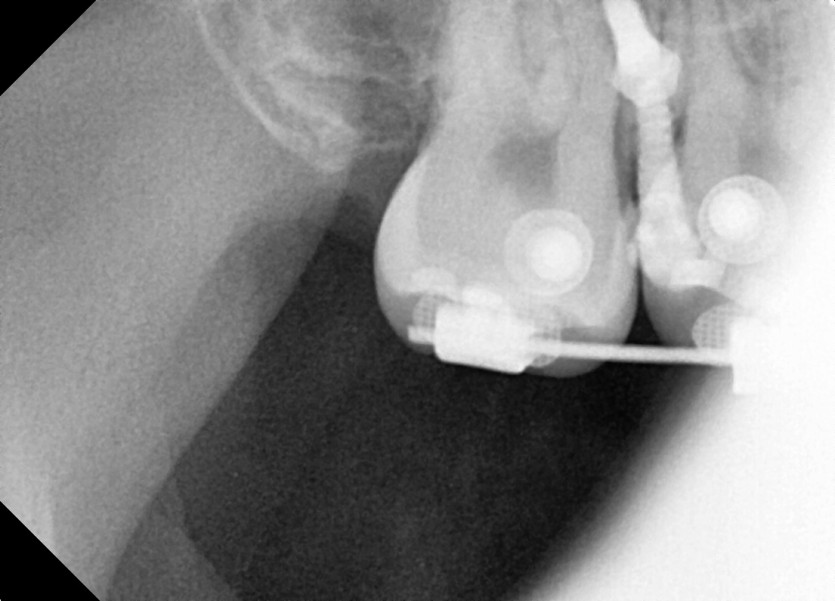

#18 사랑니 발치

구강 외과 전문의가 당일 발치했습니다.